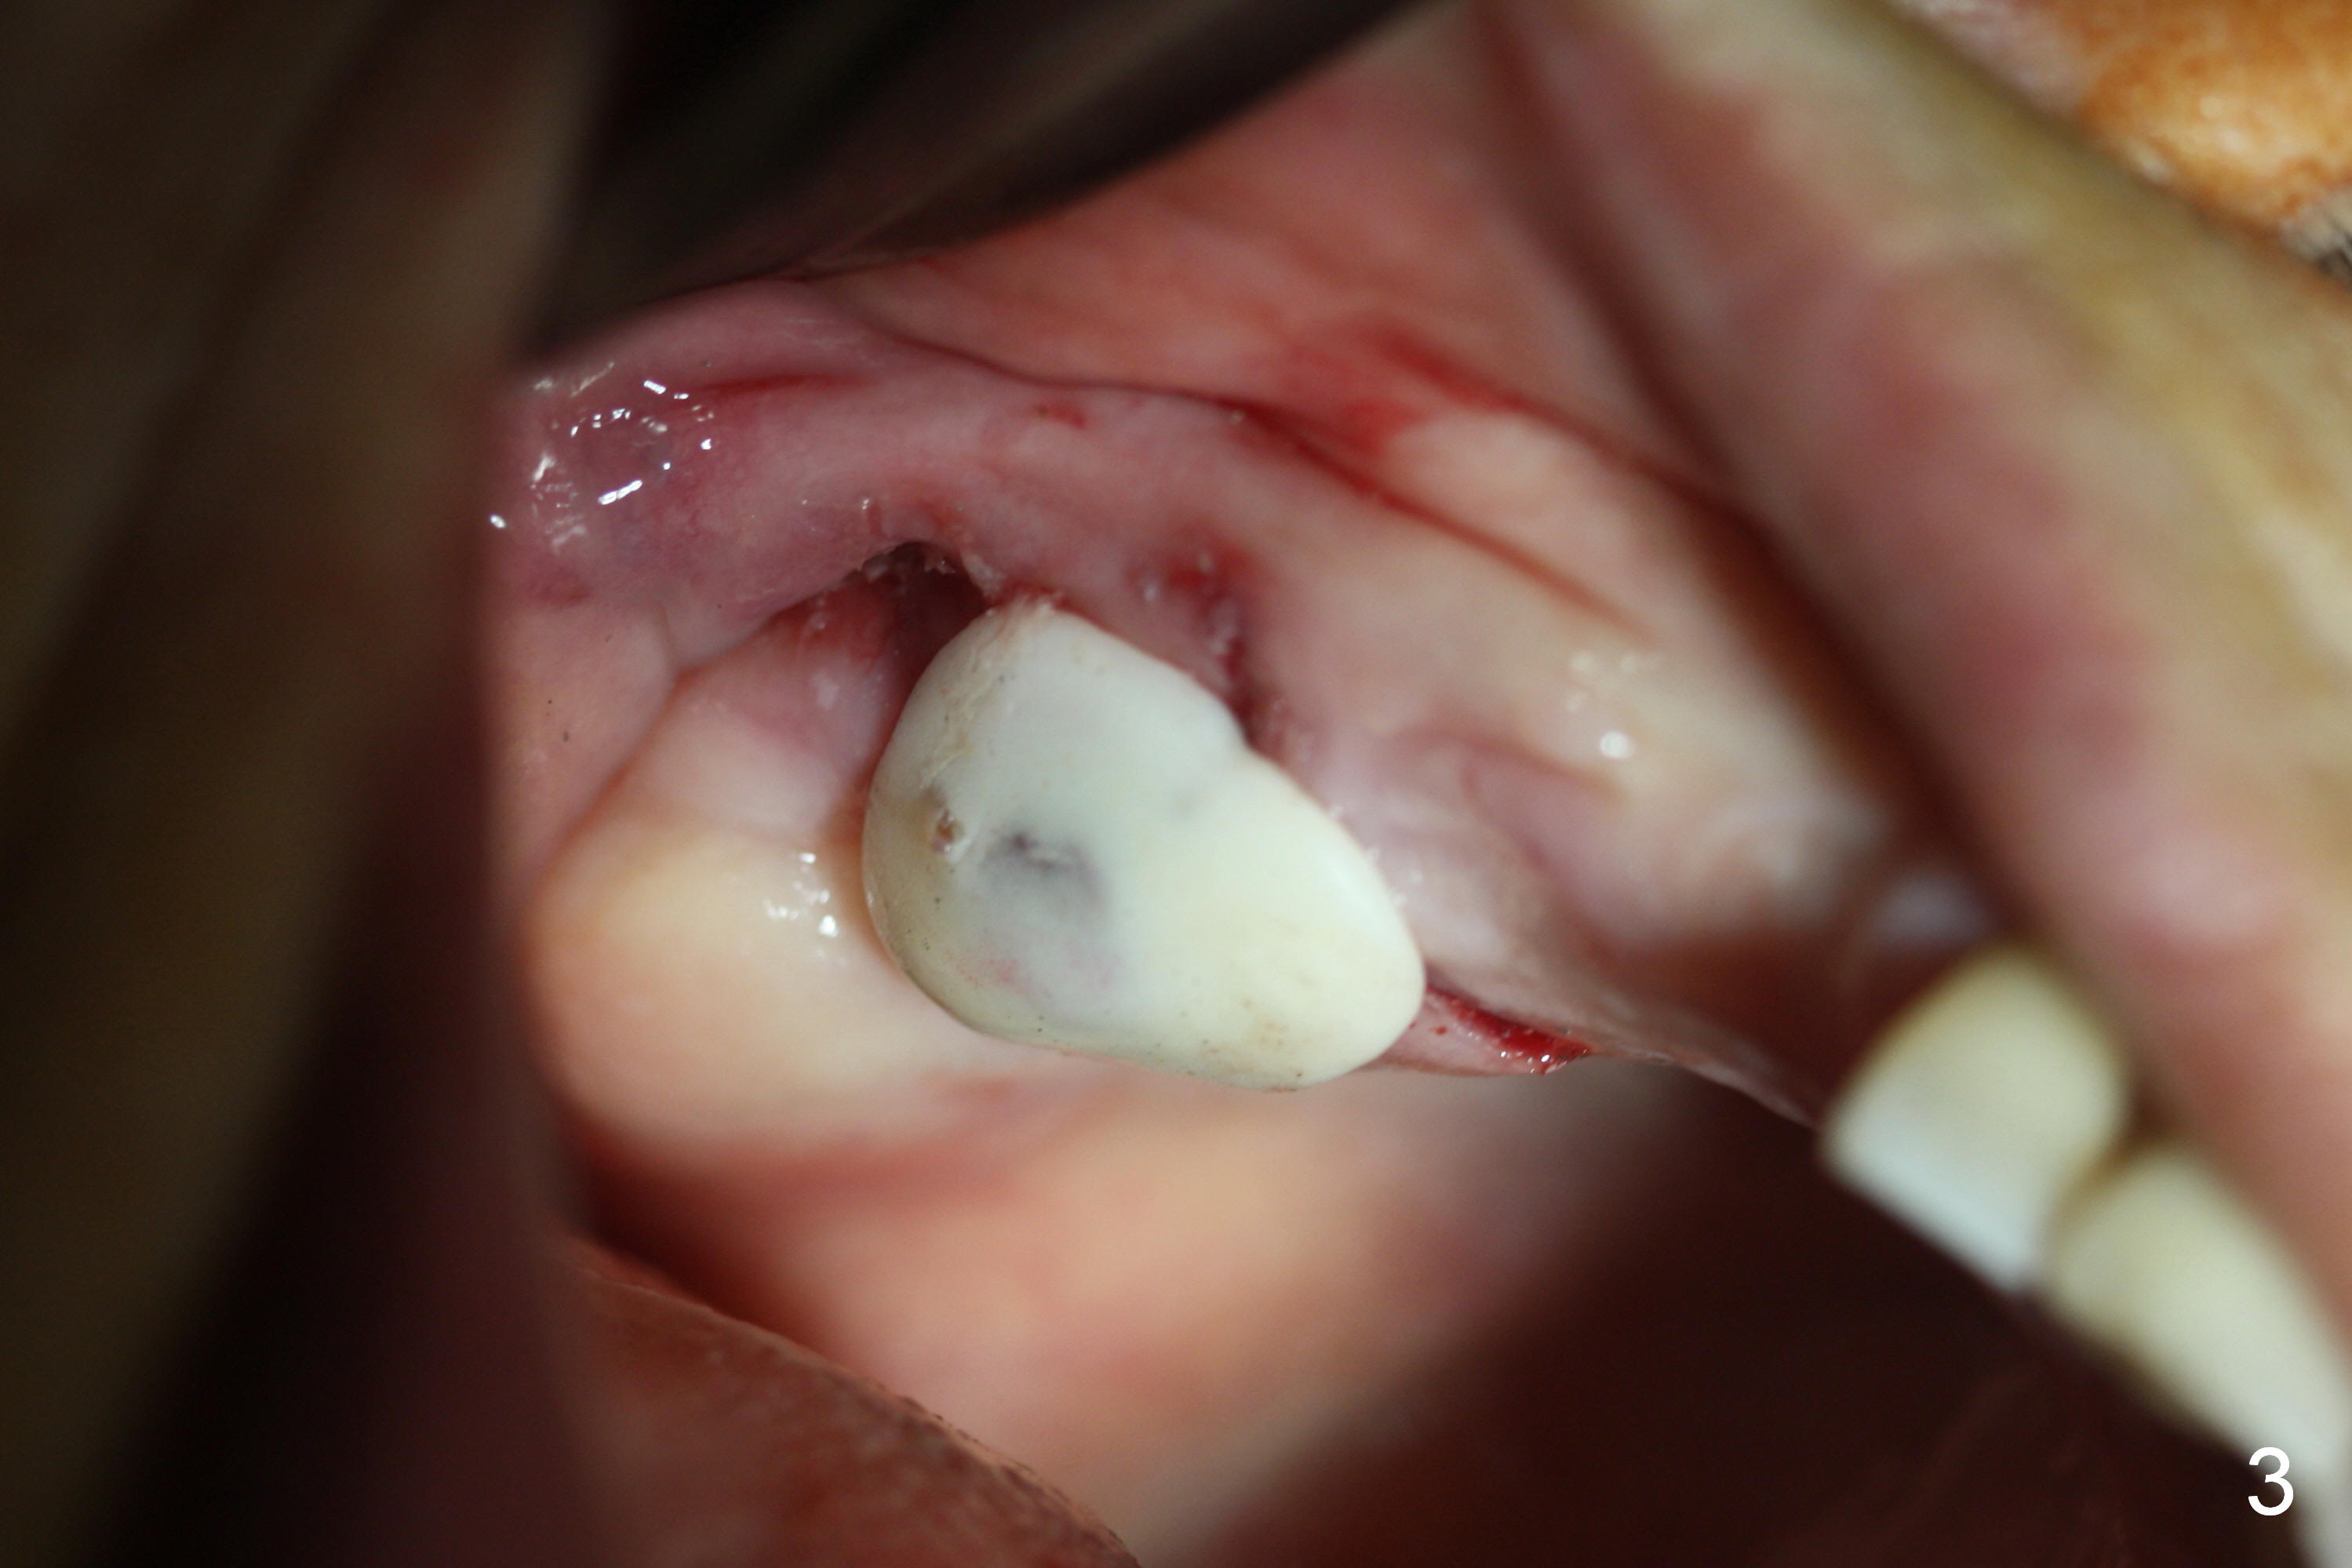

As planned, the osteotomy at #3 is underprep (using 3 mm reamer), followed by taps until 5x11 mm (Fig.1). When a 6x11 mm implant is being placed with high torque (Fig.2 (*: sinus lift)), bone mesiobuccal to the implant is starting to green-stick fracture. After flap suturing, a 5x3 mm abutment is placed and adjusted for the height. In fact the long vertical edentulous space is an artifact. An immediate provisional is fabricated with clearance (Fig.3,4). The adaptation of the provisional to the implant/abutment is so good that cement is not necessary for retention. When the wound heals, the provisional is too short to be retentive. It is not recemented. A healing screw is placed until the implant is restored.